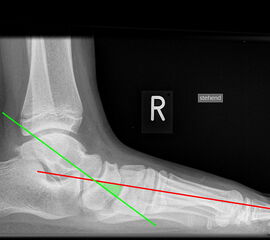

Achsen auf der lateralen Aufnahme

Die Grundlinie (blau) ist definiert durch den tiefsten Punkt der Sesambeine und den tiefsten Punkt des Kalkaneus.

CPA (Calcaneal pitch angle): Der Kalkaneus Inklinationswinkel liegt zwischen der Grundlinie (blau) und der plantaren Begrenzung des Kalkaneus (grün) (Norm 20,8 ± 4,1° 11, 15-39° (Zwipp 2014)).

LTCA (Lateral talocalcaneal angle): Der laterale talokalkaneare Winkel liegt wird gebildet aus der Talusachse (türkis) und einer Verbindungslinie zwischen dem Oberrand des Proc. ant. Calcanei und der dorsalen Begrenzung des Kalkaneus (gelb). (Norm: 33° Range 25-45°) 1213).

LTMA (Lateral talometatarsal angle, Syn. Meary’s angle): Der laterale talometatarsale Winkel wird gebildet aus der Achse des Os metatarsale I (rot) und der Achse des Talus (türkis). (Norm: 7,1 ± 10,8 11).

Böhler-Winkel (Syn. Tubergelenkwinkel)

Es wird eine Linie vom Proc. ant. calcanei zur dorsalen Facette des Subtalargelenks gezogen (rot). Die zweite Linie verläuft von der kranialen Begrenzung des Tuber calcanei zum Subtalargelenk (gelb). Gemessen wird der nach dorsal offene Winkel zwischen den beiden Linien (Norm: 22-48° 9).